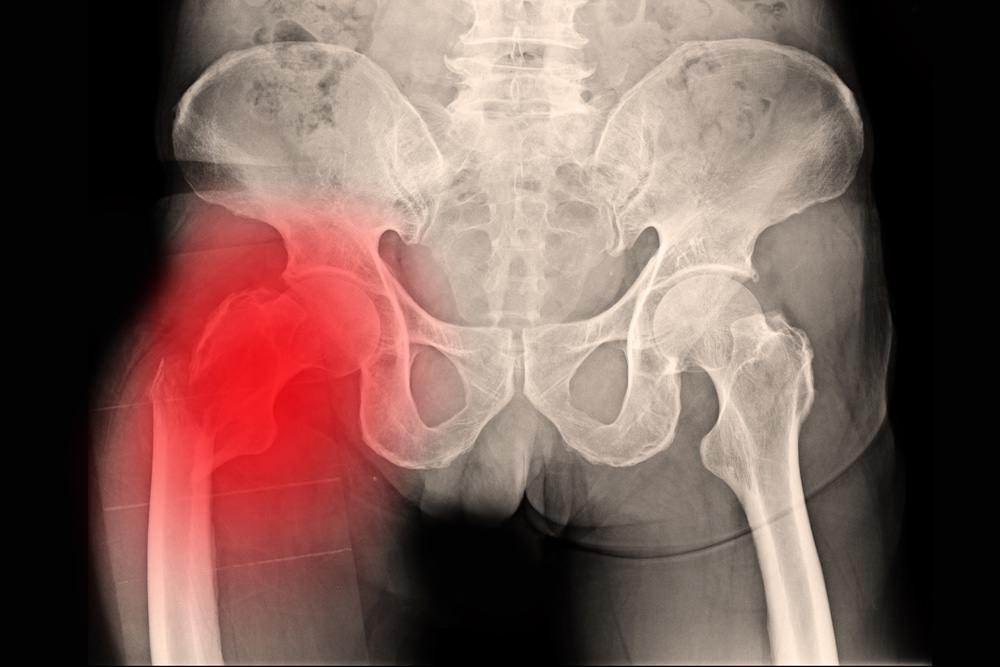

- الفحص بالأشعة: يعتبر أحد أدق التشخيصات التي قد يخضع لها المريض في العادة، فهي تكشف عن شكل العظام من الداخل والشروخ التي تعاني منها ودرجة الكسر ومدى تضرر الأجزاء الأخرى المحيطة به من جميع الاتجاهات ومن أهمها الأشعة السينية والتصوير بالرنين المغناطيسي.